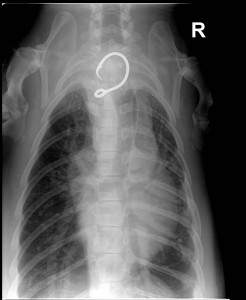

HONOLULU — The Department of Land and Natural Resources (DLNR) and the National Oceanic and Atmospheric Administration (NOAA) this morning reported that a juvenile monk seal flown by the U.S. Coast Guard from Hawai‘i Island to O‘ahu last Friday for medical treatment has died. A necropsy conducted by NOAA Fisheries revealed that the young male seal, known by his ID tags as RK68, suffered fractured ribs earlier in life, but ingestion of a fishing hook more recently is believed to be the cause of death.

Results of the necropsy reveal that the seal may have been hooked for several weeks or months. Officials believe had they received a detailed report of the hooking incident when it occurred, the chances of a life-saving response could have been much greater.